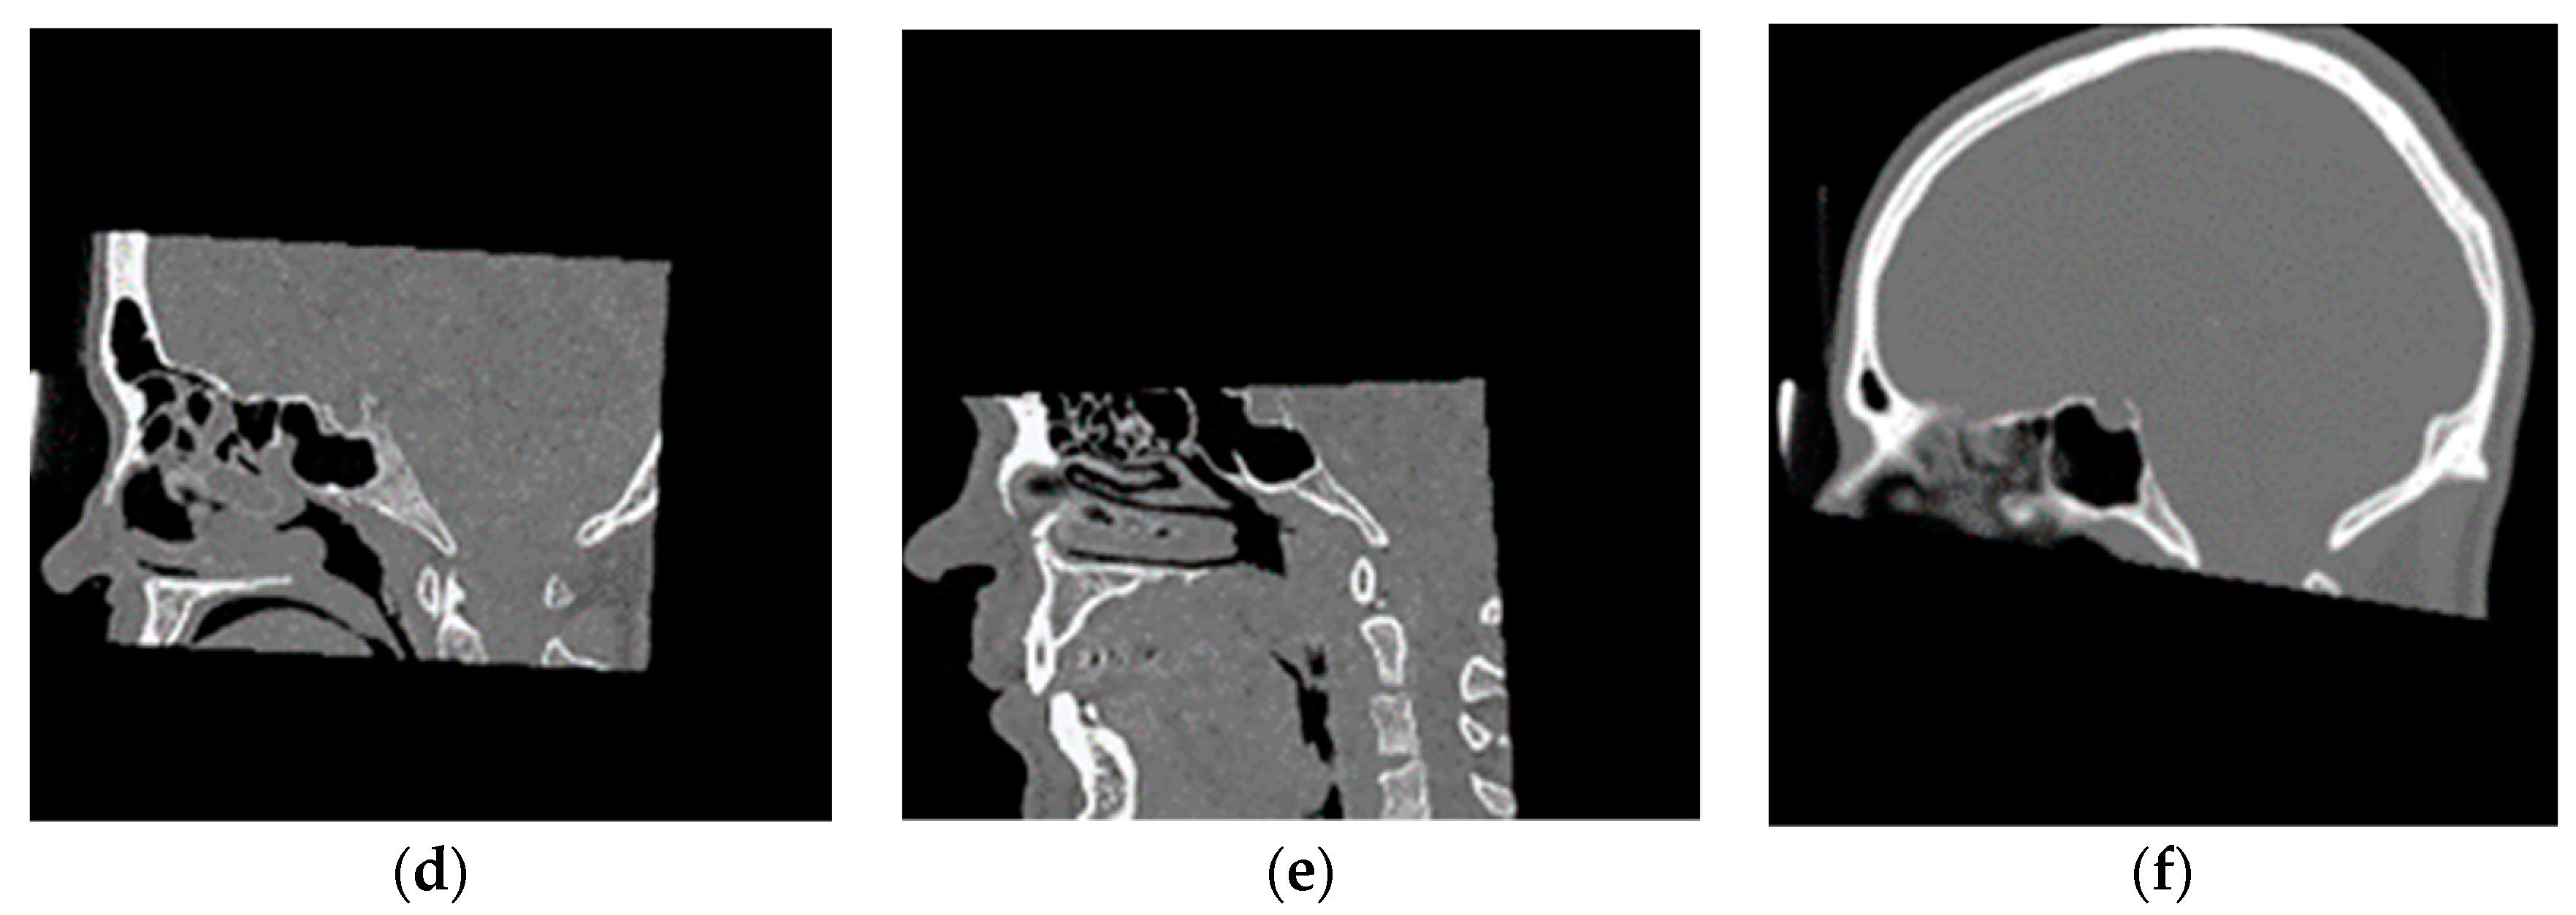

2.1. Franken-Computerized Tomography (Franken-CT) Approach

2.2.1. Training Dataset

3.2. Franken-CT Approach Results